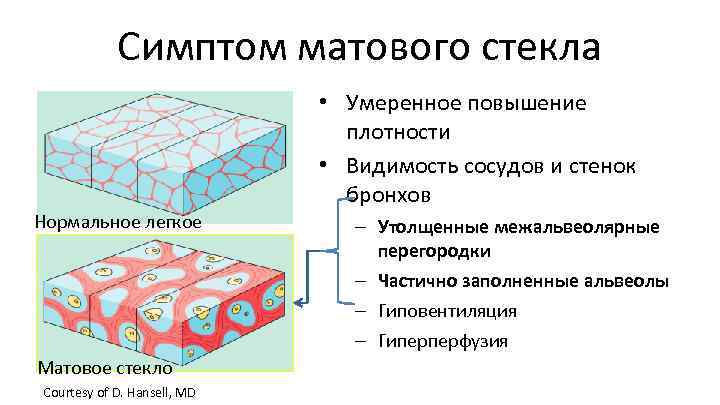

Симптом матового стекла • Умеренное повышение плотности • Видимость сосудов и стенок бронхов Нормальное легкое Матовое стекло Courtesy of D. Hansell, MD – Утолщенные межальвеолярные перегородки – Частично заполненные альвеолы – Гиповентиляция – Гиперперфузия